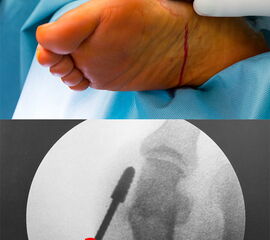

• Sämtliche Osteotomien werden in der sogenannten „Safe-Hole-Technik“ durchgeführt: Perforieren der ersten Kortikalis mit der Fräse, so dass der schneidende Anteil der Fräse intramedullär zu liegen kommt. Nun kann die Osteotomie aus dem Markraum heraus komplettiert werden ohne Gefahr einer akzidentellen Verletzung umliegender Strukturen.

Die minimalinvasive Chirurgie (MIS – Minimal invasive surgery) ist geprägt von einigen Spezifika, die ein Umdenken des in der offenen OP-Technik routinierten Operateurs erforderlich machen. Der grundlegende Unterschied für den Operateur besteht darin, dass das OP-Gebiet nicht direkt eingesehen werden kann. Daher ist die Kenntnis der anatomischen Strukturen und der daraus resultierenden Zugangswege und OP-Techniken von besonderer Bedeutung.

Ein vollständiges Umdenken und Umlernen ist erforderlich für den Chirurgen, der in der offenen OP-Technik mit dem Leitspruch groß geworden ist: „Nie schneiden, wo man nichts sieht!“, da die intraoperative Kontrolle des eigenen Tuns in der MIS ausschließlich über Durchleuchtung mit dem C-Bogen erfolgen kann.